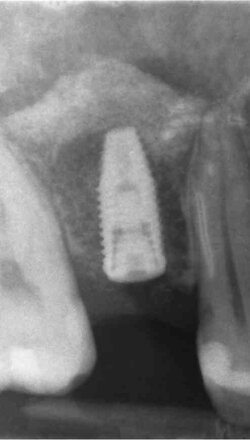

Implantologia Guidata: chirurgia mini-invasiva di alta precisione.